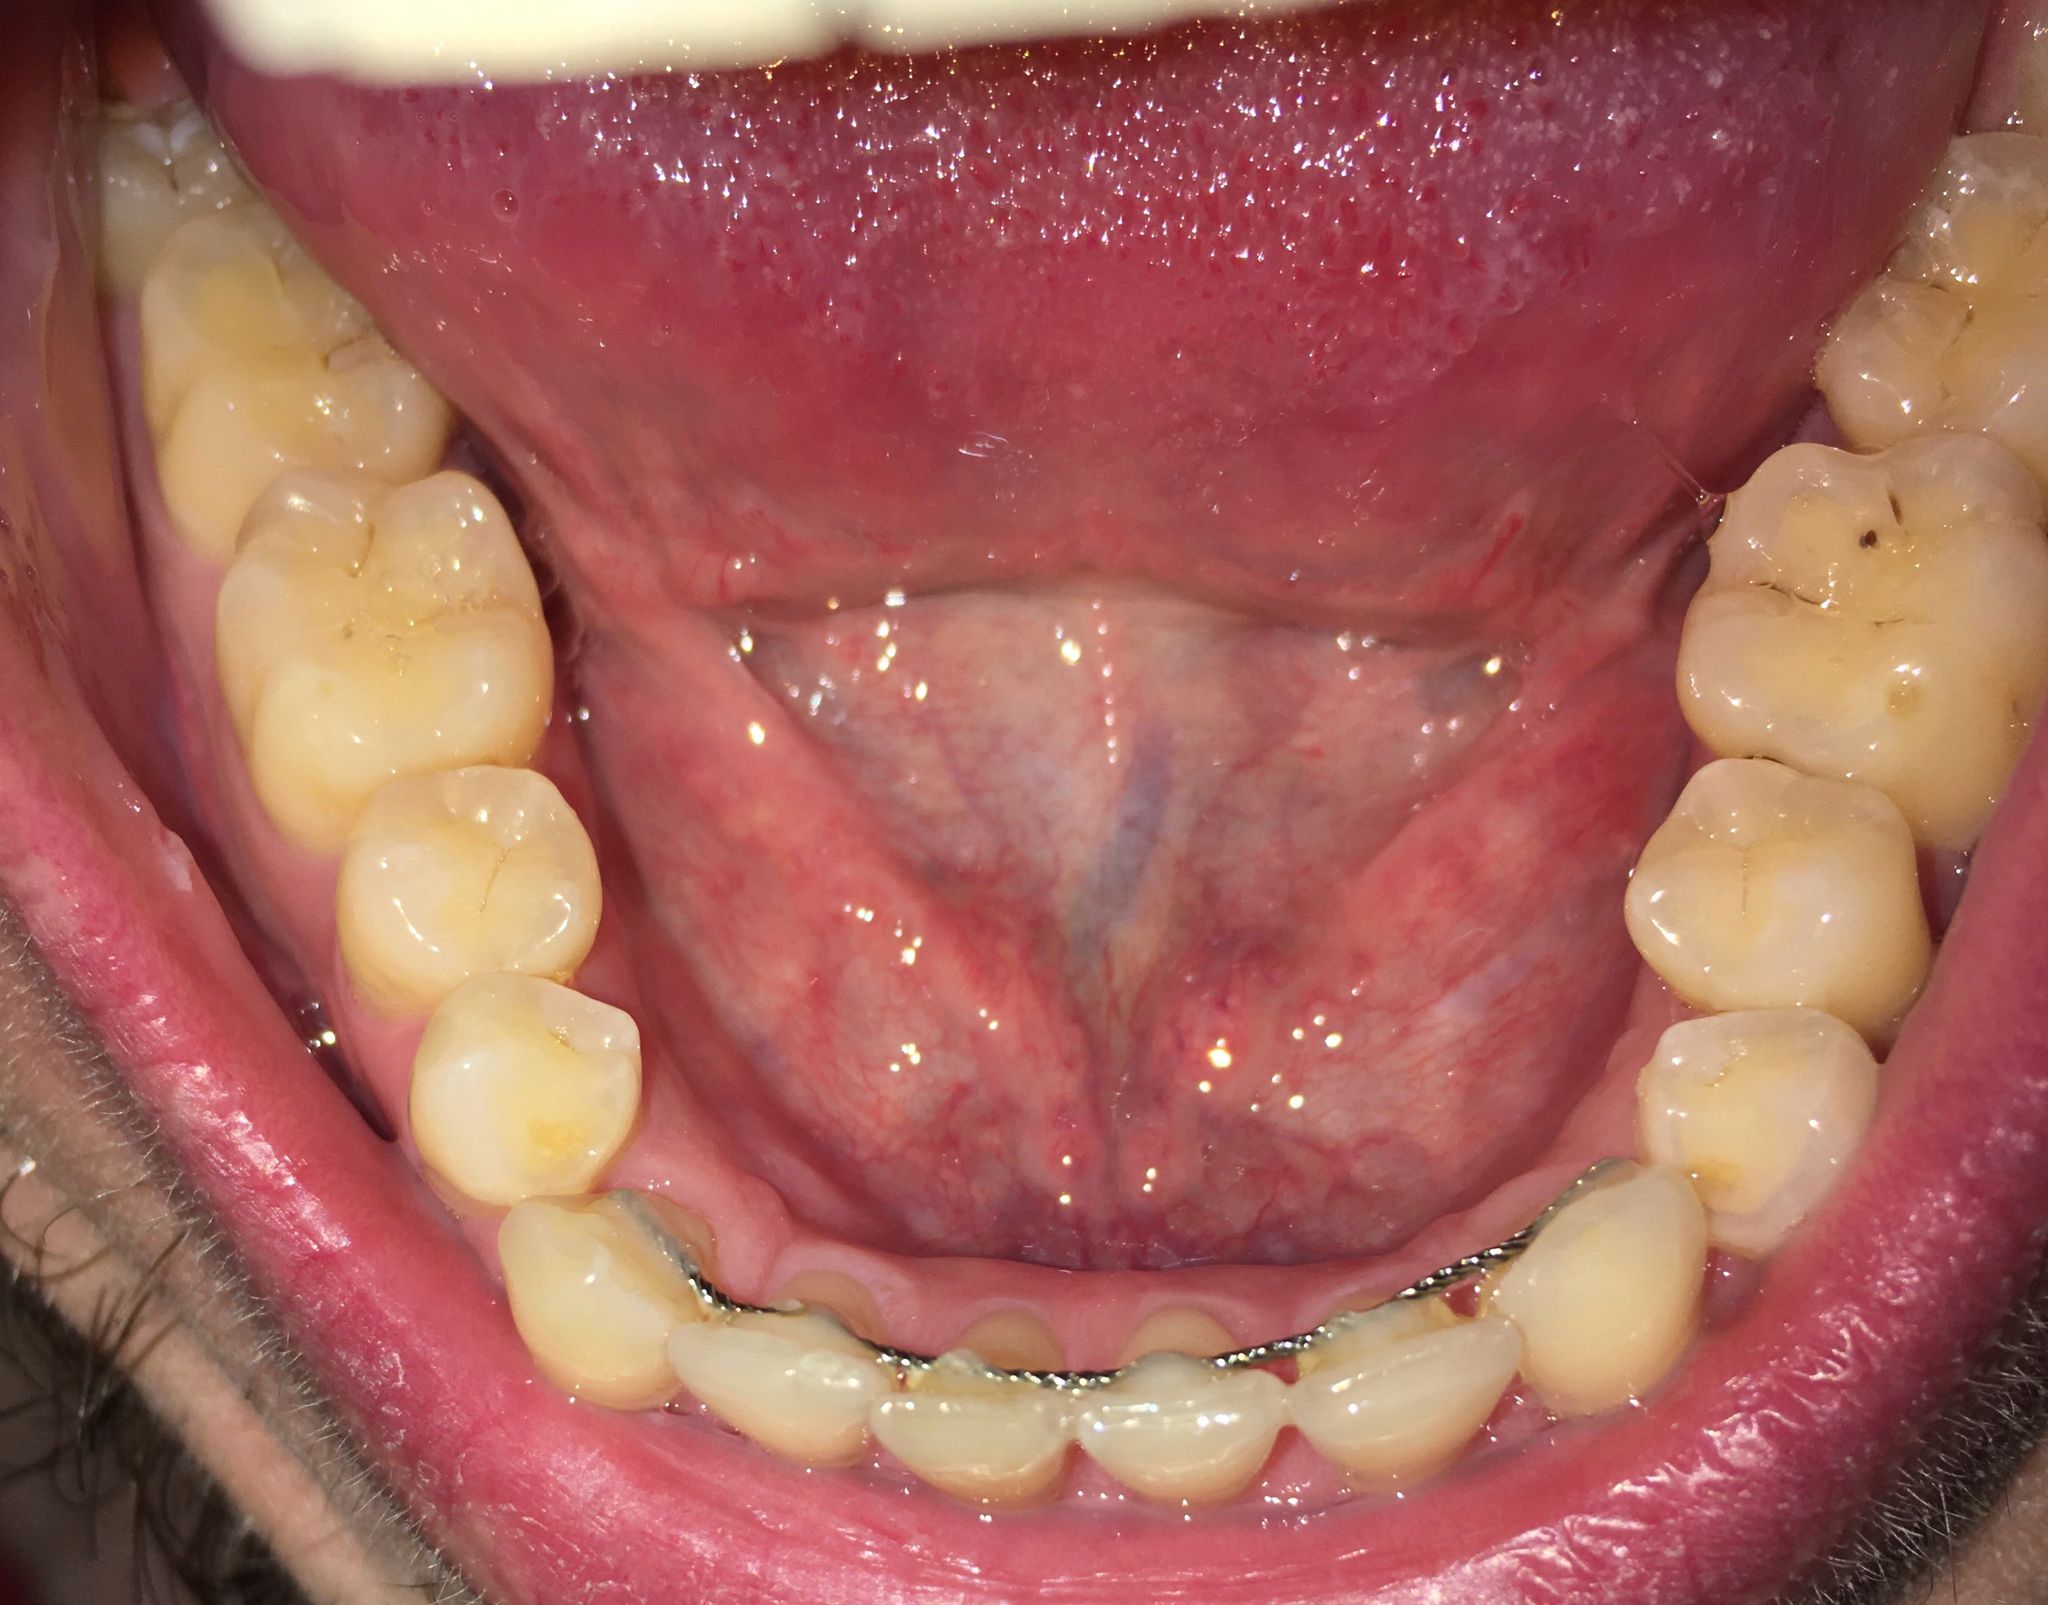

De laatste foto is ook van vandaag, van de ondertanden. Moet ik me zorgen maken?

Hierbij 3 foto's van mijn onderkaak. De eerste foto is van mijn linker onderkaak van 2017, de tweede foto is van mijn rechter onderkaak van 2017 en de laatste foto is van 2015 van mijn gehele onderkaak. De foto van 2015 is met een andere telefoon genomen, hierdoor is de kleur en belichting wat anders, echter zie ik bij alle drie de foto's en de foto van 2025 de zelfde hoeveelheid doorzichtigheid.